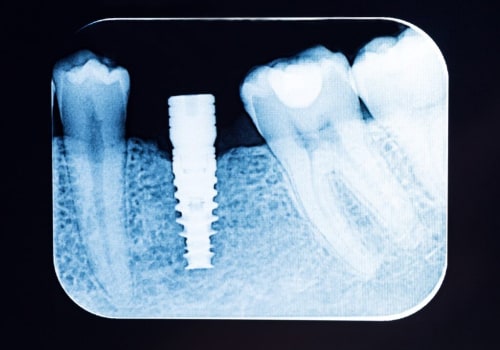

How Dental X-Rays Help Prevent Complications During Implant Surgery In McGregor, TX

Dental implants are a popular option for restoring lost or damaged teeth, but like any surgical procedure, there are...

Understanding The Importance Of Dental X-Rays Before Getting A Dental Implant In Georgetown

Dental implant surgery in Georgetown is an excellent way to replace missing teeth and restore your smile. In order for it ...

Why Are Dental X-Rays Required When Obtaining Dental Implants In Austin

Getting dental implants in Austin is a great way to restore your smile and confidence. In order to ensure that you are...

The Journey Of Dental Implants And The Crucial Role Of Dental X-Rays In Schertz, TX

Advancements in dental technology have revolutionized the field of dentistry, providing patients with innovative...